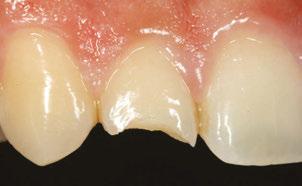

Several clinical solutions exist for primary anterior teeth with multisurface decay. Full coronal restoration of carious primary incisors may be indicated when caries is present on multiple surfaces, pulpal therapy is indicated, caries may be minor, but oral hygiene is very poor, or in a child with severe early childhood caries or a high caries risk diagnosis.1 Depending on the clinical scenario, a minimally invasive approach with the utilization of a high viscosity glass ionomer cement (HVGIC), with or without the combination of silver diamine fluoride (SDF) in a strip crown form, may pause the caries progression and provide an adequate clinical solution. Resin composite strip crowns have shown 80% retention rates and adequate parental satisfaction,1-4 although composite resin strip crowns have shown lower retention rates in teeth with decay involving three or more surfaces and particularly in children with a high caries risk4-6 (Figure 1). This could be from the continued high caries risk behaviors of the patient, as composite resin strip crowns in this population have shown to have increased inflamed marginal gingiva and gingival bleeding, increased plaque retention along the restoration, and loss of some restorative material.5,6

Alternatively, a resin-faced stainless steel crown provides a full coverage restoration with excellent retention.7 These crowns can serve as a full-coverage restoration with or without the resin facing, but the loss of resin facing can be a major esthetic concern for parents.7 Preformed pediatric zirconia crowns address many of the undesirable clinical outcomes of other restorative materials. Their biocompatibility, demonstration of excellent marginal gingival health, low plaque retention, high parental esthetic acceptance, and high survival probabilities make them an excellent clinical choice in the patient with severe early childhood caries.1,4,5,8-13

With parental interest increasing in esthetic treatment options for complex anterior caries, preformed pediatric zirconia crowns are becoming the treatment of choice for patients with a high caries risk or a severe early childhood caries diagnosis.14

This review discusses three clinical cases in which NuSmile® ZR (NuSmile, Houston, Texas) anterior pediatric zirconia crowns were the correct clinical decision in varying clinical scenarios.

around these clinical sites. His anterior zirconia crowns showed healthy gingival margins with little-to-no plaque accumulations. This positive clinical finding is from the highly polished nature and biocompatibility of pediatric zirconia crowns. These restoration features limit plaque accumulations on the restoration and along the marginal gingiva, providing a localized positive aspect directly related to the choice of restorative material (Figure 2).

A 3-year-old female presented with pulpal necrosis and abscess on #E and pulpal necrosis on #F. Extraction therapy or pulpectomy was offered. The family was highly motivated to retain #E and #F. The pulpectomy was performed with 0.02 K-Flex hand files, 3% NaOCl with a lateral vented needle, obturated with Vitapex (Neo Dental International Inc., Federal Way, Washington), a premixed paste of calcium hydroxide and iodoform. The access was filled with a HVGIC sealing the pulp therapy and increasing the clinical success by minimizing the potential for bacterial contamination. NuSmile ZR anterior crowns were selected as offering a full-coverage, esthetic, cemented restoration with no polymerization shrinkage when compared to a composite restoration. Crowns were cemented with NuSmile® BioCem (NuSmile, Houston, Texas). This is clinically beneficial as the provider would want to cement a restoration that provides limited microleakage minimizing the potential for bacterial contamination.15-17 At 6-month follow up, lesion healing had occurred with healthy gingival margins and no plaque accumulations (Figure 3).

had been previously treated using SDF and covered with a HVGIC in a strip crown form. Though her lesions were stable from the clinical success of the SDF and HVGIC, these restorations were starting to fracture and demonstrate loss of material. The family wanted a more esthetic treatment option that would have a longer survivability. Additionally due to her high caries risk nature, a full coverage restoration with NuSmile® ZR anterior crowns were a more ideal solution in stabilizing her extensive decay pattern and covering staining from SDF therapy (Figure 4).

Figure 3: NuSmile® ZR Crowns were selected as a cementable full coverage restoration. At 6-month recall, apical tissues were healed with excellent gingival health Figure 4: SMART style restorations that were definitively restored with NuSmile® ZR Crowns as an esthetic option to cover SDF staining